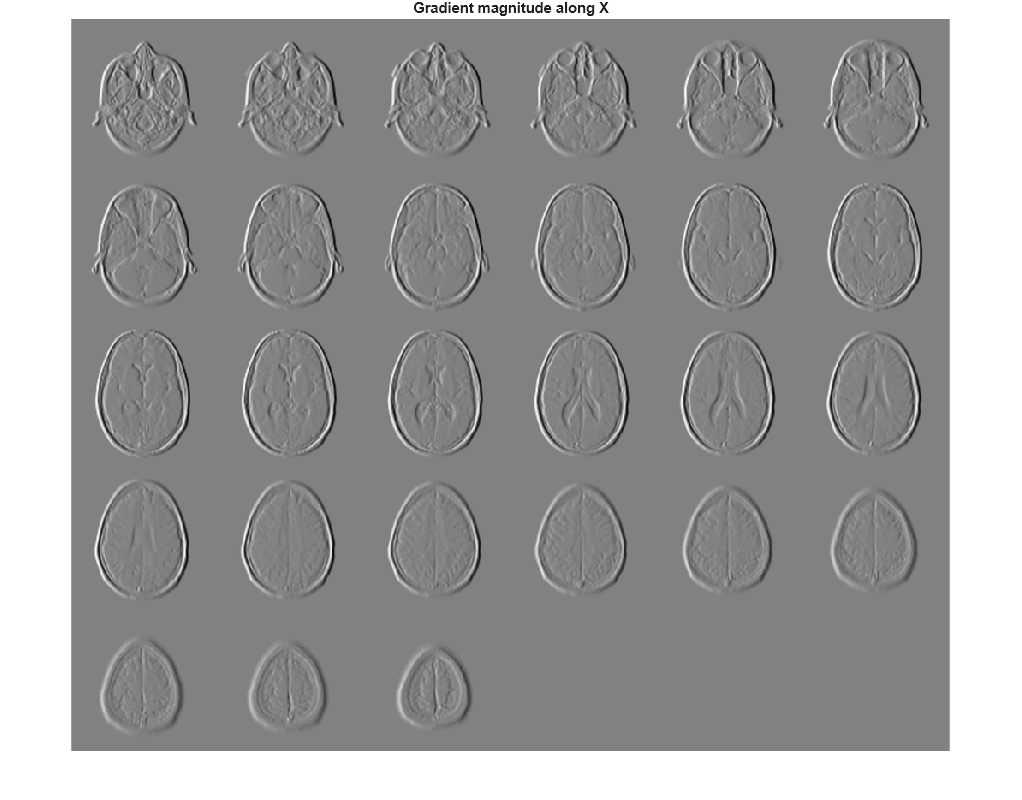

Visualize the directional gradients as a montage.

figure, montage(reshape(Gx,sz(1),sz(2),1,sz(3)),'DisplayRange',[]) title('Gradient magnitude along X')